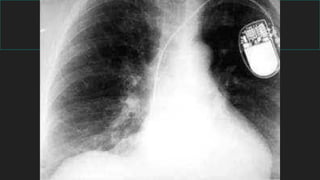

INSUFICIENCIA CARDIACA

Recuerde los 4 signos radiológicos:

 1) Lineas B Kerley

 2) Congestión peribronquial

 3) Liquido en las cisuras

 4) Derrame pleural

 CARDIOMEGALIA